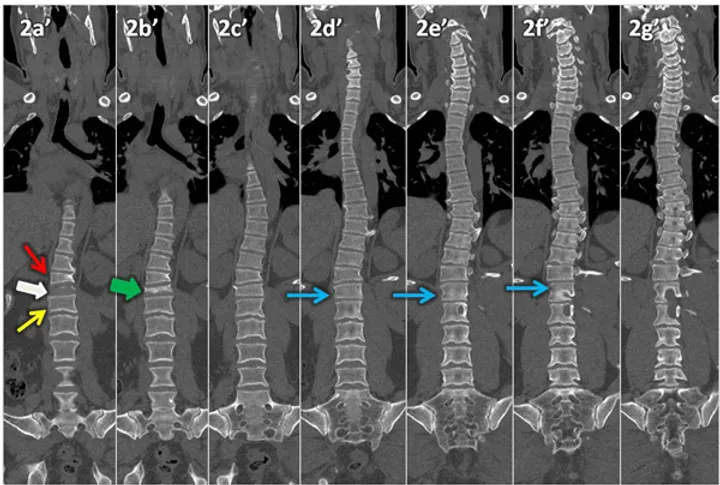

Figura 2 (a-g): Reconstrução tomográfica com a técnica MPR curva da coluna vertebral no plano coronal de anterior (2a) para posterior (2g).

Figura 2 (a-g)’: Reconstrução tomográfica com a técnica MPR curva da coluna vertebral no plano coronal de anterior (2a’) para posterior (2g’) onde se nota ausência da porção anterior do corpo vertebral L1 (seta branca), que só é individualizado na metade posterior (setas azuis). Há também redução da altura da porção anterior dos corpos vertebrais T12(seta vermelha) e L2 (seta amarela), que têm altura normal na porção posterior.